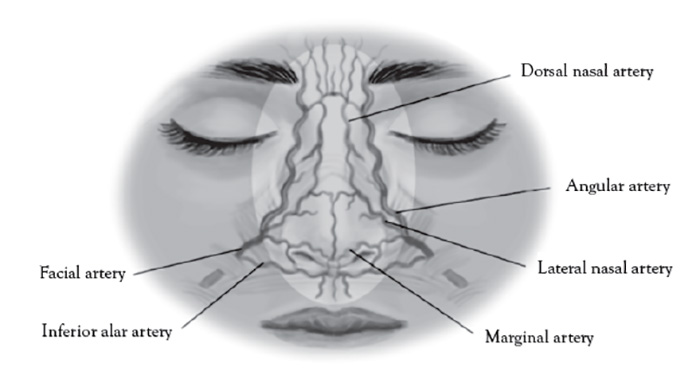

The nasal and paranasal small network of arteries are too small in caliber and not amenable to conventional color Doppler ultrasound not otherwise equipped with power Doppler capability.

The dorsal nasal artery is a terminal branch of the ophthalmic artery and emerges from the medial orbital rim along the nasal septum [138]. The angular artery is the terminal portion of the facial artery and located at the lateral margin of the ala of the nose [138].

The paranasal area becomes a target in aesthetic practice, particularly with regard to injection of cosmetic fillers in achieving a "liquid rhinoplasty" or nasal contouring (Figure 7).Unlike other areas of cosmetic filler injections, midline nasal injections should be injected deep rather than superficial, because vascularity is more superficial, avoiding nasal bridge and ala [139]. Safe zones include midline middle third and lateral zone between the borders of the lateral nose and nasofacial groove. Avoid superficial injections of the alar tip and alar groove (avoid the crease) [139]. Nasal injection is the leading cause of tissue necrosis (Figure 8) [139,140].